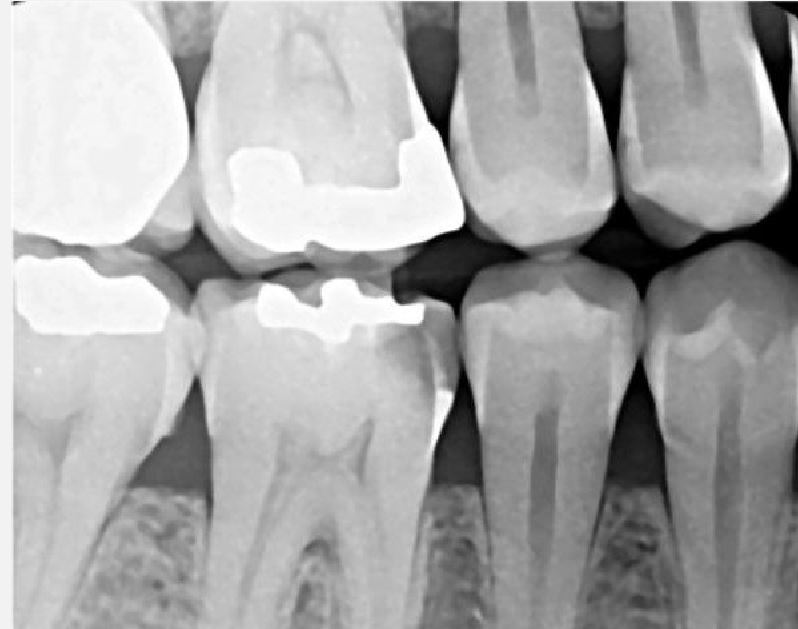

X-Ray 1: How many caries are present?

(Required)

X-Ray 1: How many PAP's are present?

X-Ray 2: How many caries are present?

X-Ray 2: How many PAP's are present?